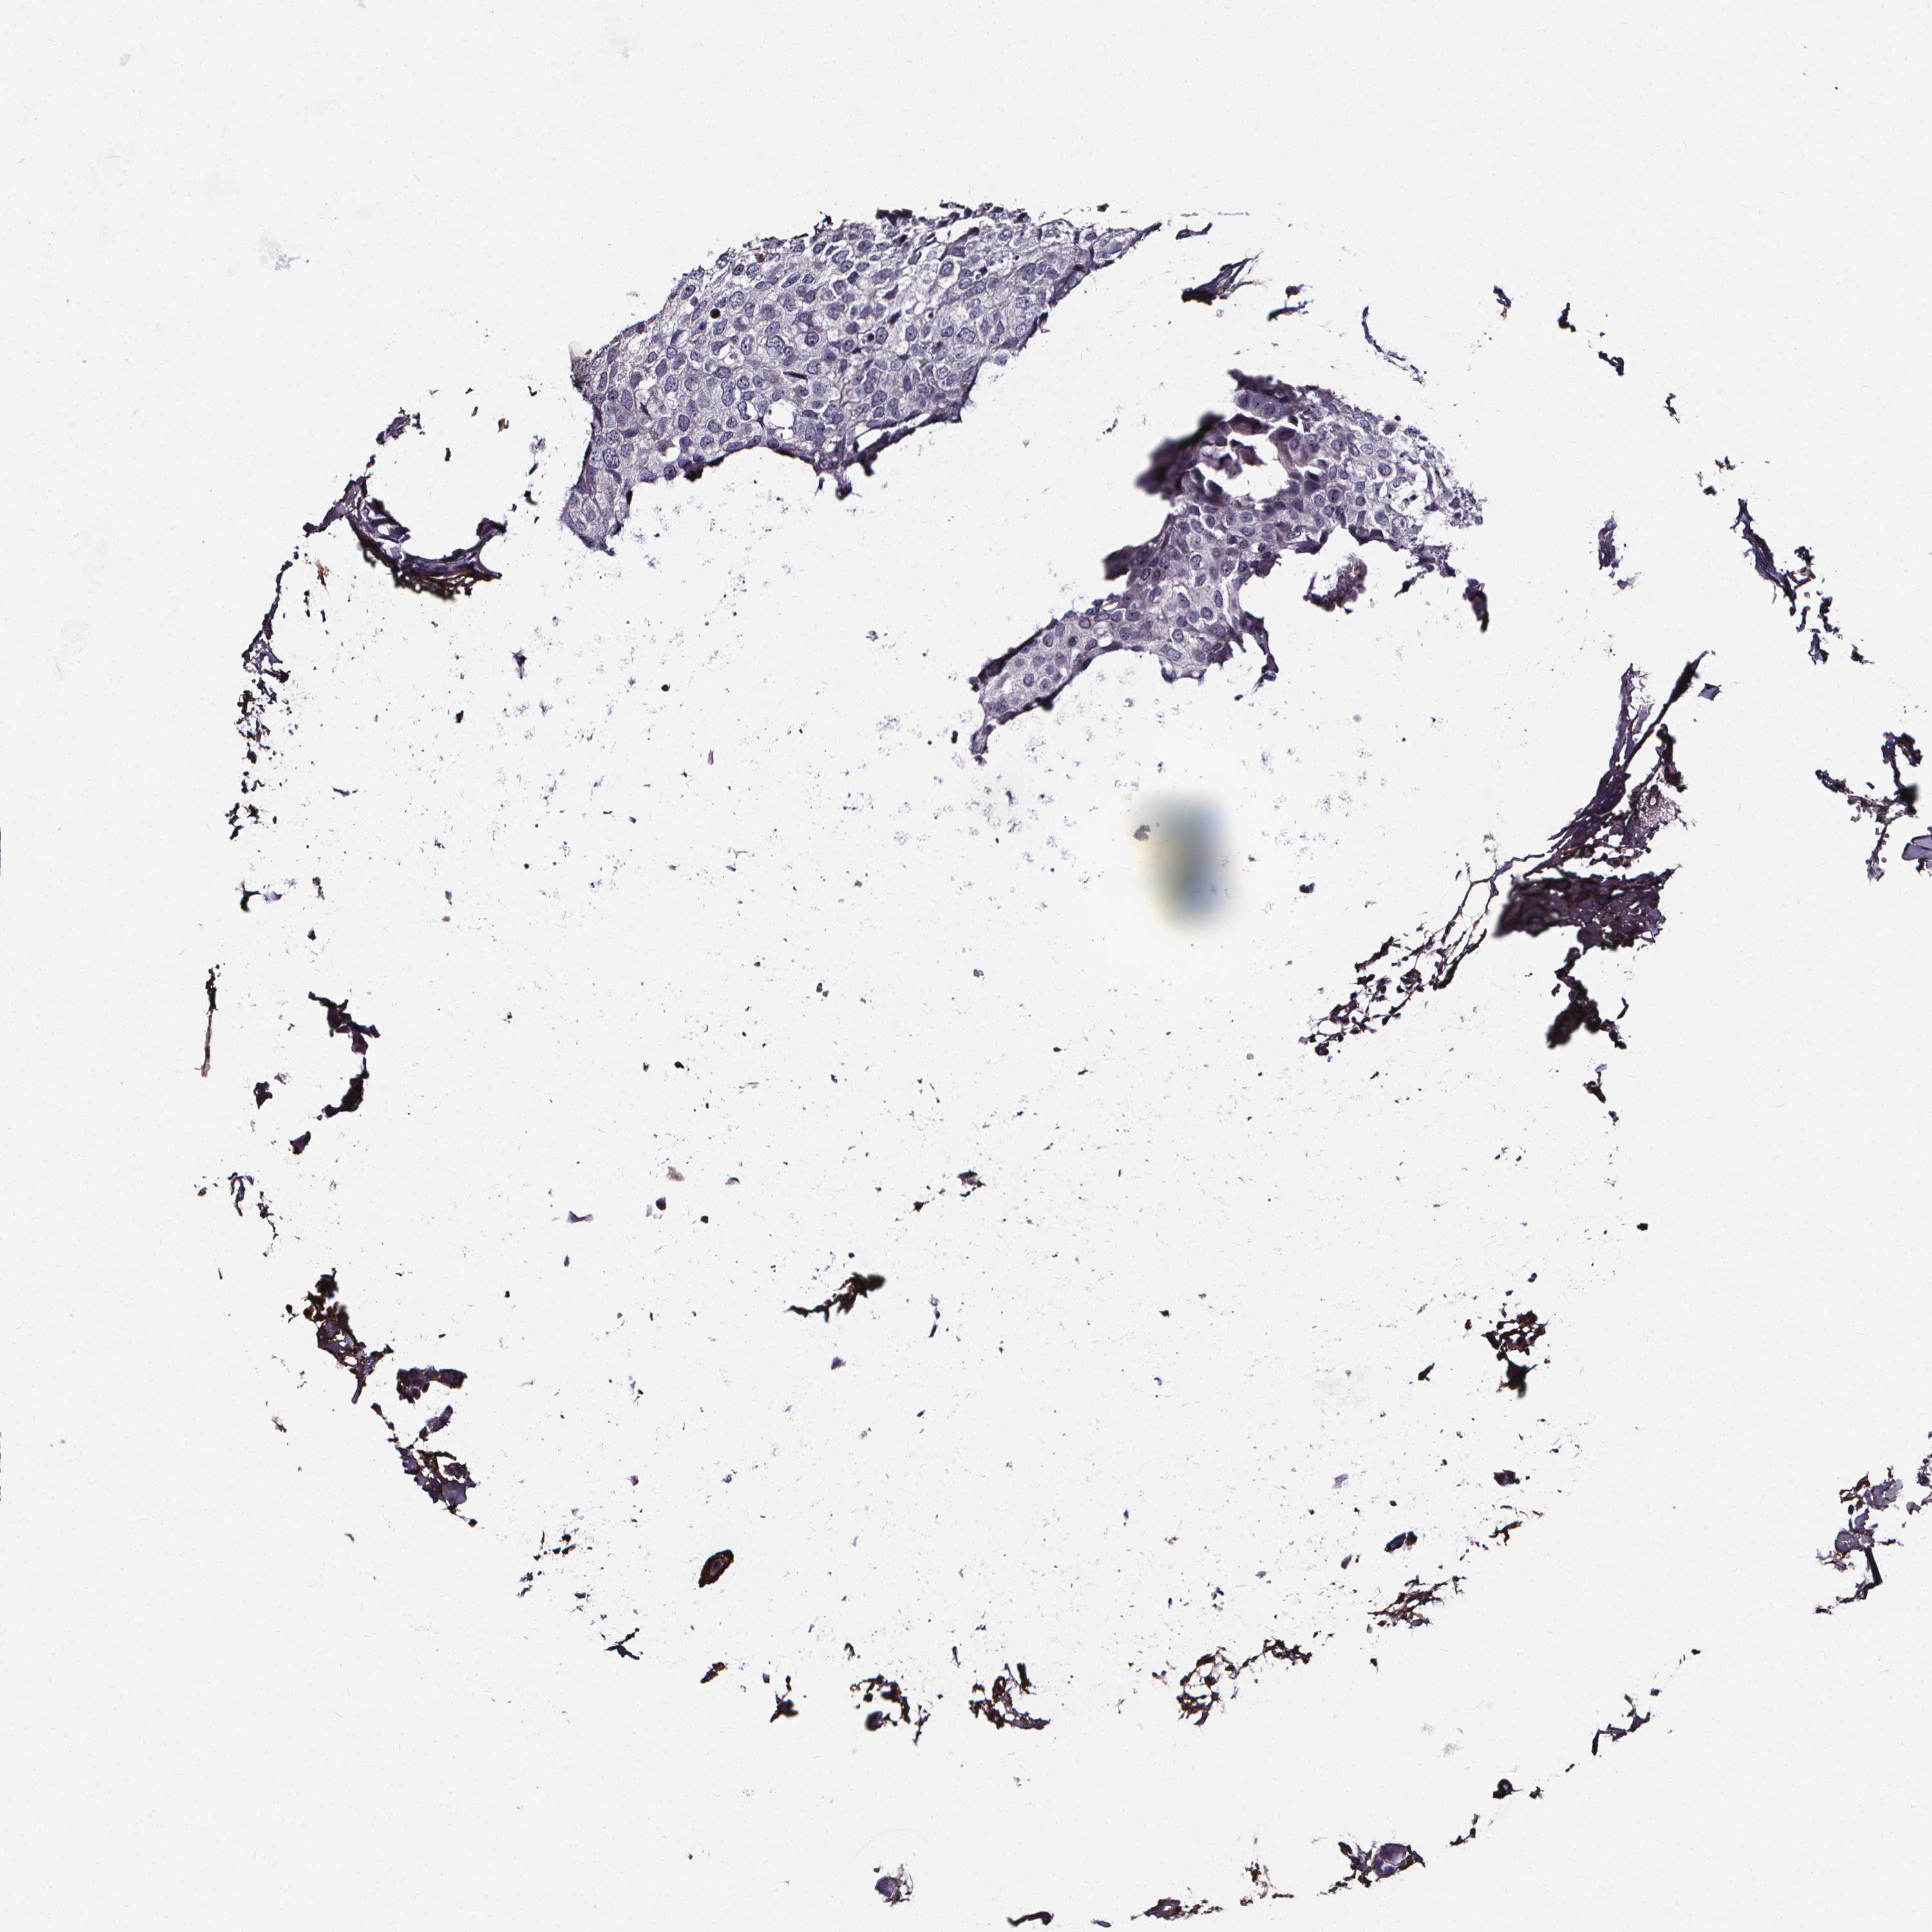

CANCER BREAST CANCER Show tissue menu

BRCA TCGA BRCA VALIDATION PROTEIN EXPRESSION